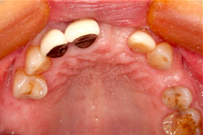

A 65-year-old female on antihypertensives and immunosuppressants presented with severe gum swelling, inability to chew, and difficulty maintaining oral hygiene. This led to multiple decayed and periodontally compromised teeth, worsening her overall condition.

Before Treatment

- Non-surgical periodontal therapy was performed to reduce gingival inflammation and swelling

- Surgical removal of excessive gum tissues and extraction of multiple poor prognosis teeth were carried out as well

- She was kept under strict follow up and advised to comply with meticulous oral hygiene measures throughout treatment